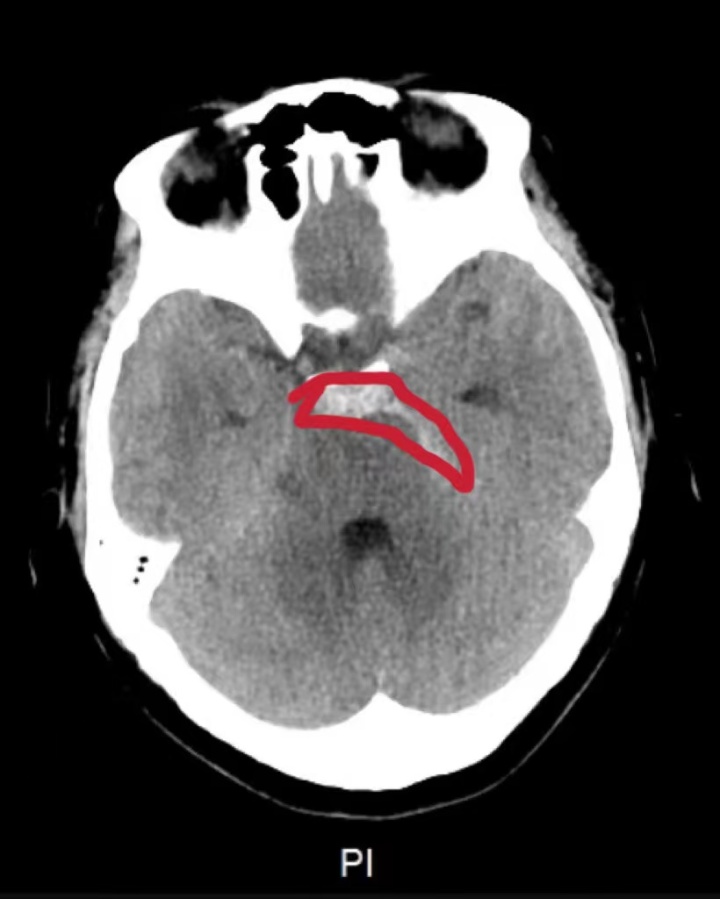

医生接诊时,林女士的情况已不容乐观,头痛反复发作,伴有呕吐,逐渐陷入嗜睡状态。检查后发现其颅内长有异常占位,且已发生出血,同时右侧脑部积水呈进行性加重趋势,必须立即进行医疗干预。医生果断决定,为林女士实施急诊手术,切除颅内的异常占位。

医生介绍,林女士所患的是一种特殊的脑血管病——脑动脉瘤破裂引发颅脑出血疾病,该病起病急骤,往往快速恶化达峰,不给病患和家属反应时间,其高致残率及高致死性结局往往给病患及其家属带来严重的伤害。